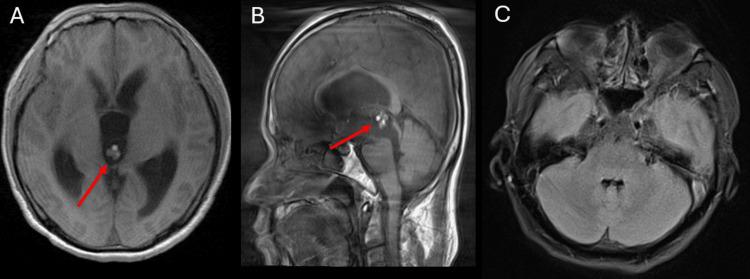

Neurocysticercosis is a parasitic infection of the central nervous system commonly caused by . Imaging with magnetic resonance imaging (MRI) is critical for diagnosis and follow-up of the infection. In this report, we present the case of a 44-year-old male with a history of chronic neurocysticercosis who presented with acute neurological symptoms. An initial MRI showed new obstructive hydrocephalus due to a cyst in the third ventricle. The patient underwent placement of an external ventricular drain to relieve the obstructing hydrocephalus. Follow-up imaging revealed interval migration of the cyst to the fourth ventricle. The cyst was removed surgically, and the patient recovered without any complications. This case emphasizes the importance of timely imaging for effective surgical planning of neurocysticercosis.

摘要